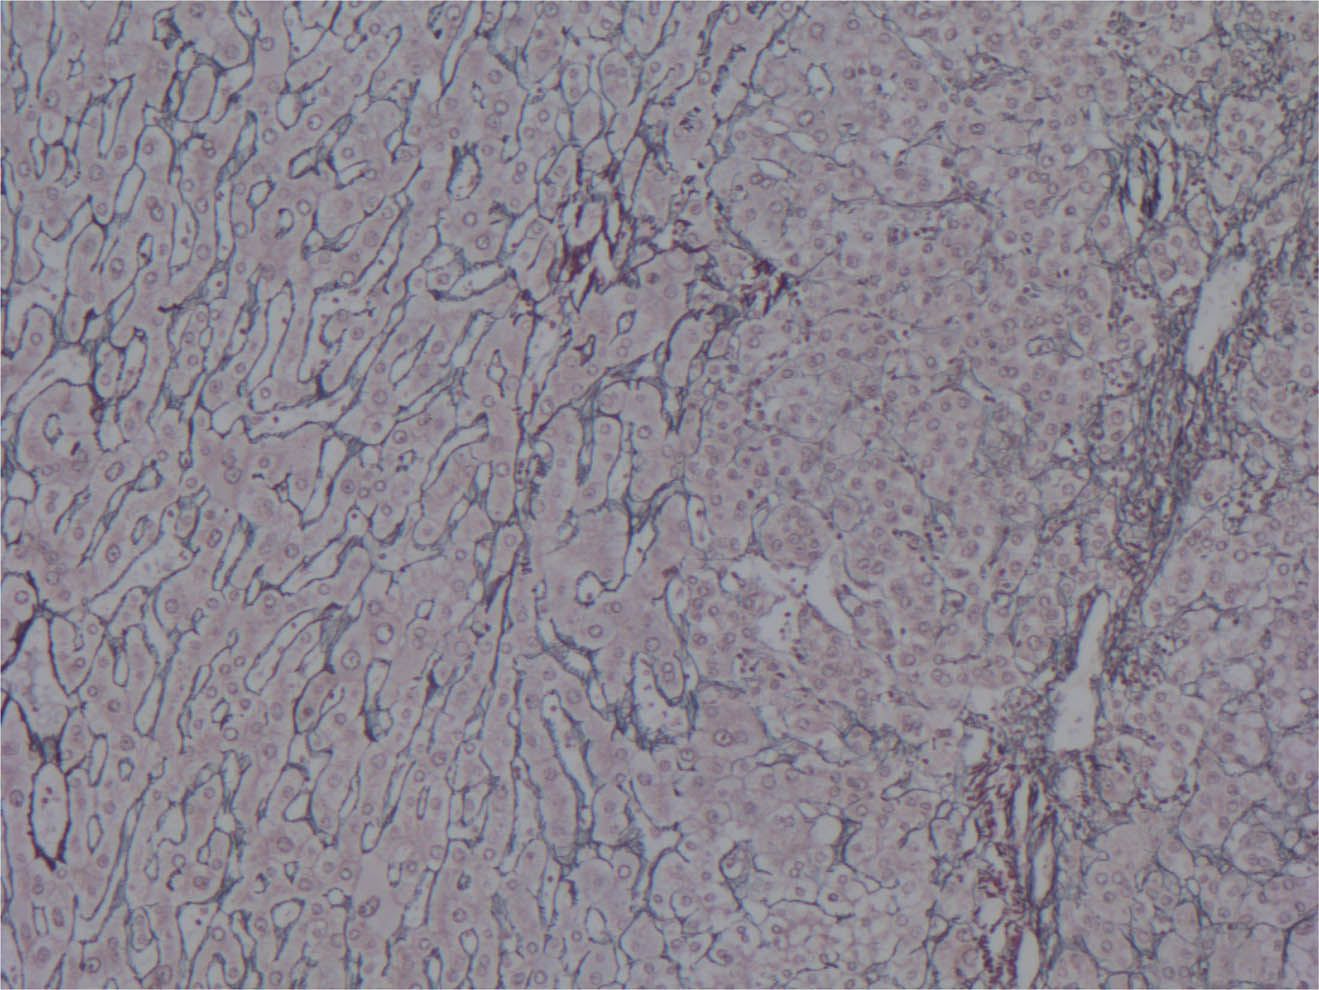

Other preneoplastic lesions include clonal proliferation of hepatocytes forming hepatocellular adenomas. These lesions are characterized morphologically by well circumscribed proliferation of bland hepatocytes with intact hepatic plates and absence of portal triads. The real differential in this situation includes mostly a well differentiated hepatocellular carcinoma. Ancillary studies such as immunohistochemistry for CD34 demonstrating complete capillarization of the sinusoids, immunohistochemistry for Glypican-3 and reticulin stain (Figure 2) are helpful for differential. Hepatocellular adenomas are occasionally linked to oral contraceptives (28). Other possible etiologies include the use of clomiphene (used as hormonal treatment for infertility issues) (29), methyltestosterone (anabolic steroid) (30) and danazol (synthetic androgen used for treatment of endometriosis) (31). At the molecular level, hepatocellular adenomas are subdivided based on HNF1a mutations (steatotic adenomas), IL-6 ⁄ STAT3 mutations (inflammatory adenomas), and β-catenin mutations (subgroup of inflammatory adenomas and unclassified adenomas with cytological atypia) (32). Prognostic implications justify such subtyping with inflammatory adenomas being frequently associated with metabolic syndrome, liver steatosis and alcohol exposure (33), and the β-catenin mutated adenomas immunophenotypically represented by nuclear staining associated with a higher risk of malignancy. Extensive literature and classification of hepatocellular adenomas is available, but the key is the identification of the lesions with great risk of progression to hepatocellular carcinoma.

Fig 2

Figure 2. Reticulin stain 200X. On the left, normal hepatocytes with one to two cell thick hepatic plates as compared to hepatocellular carcinoma (on the right) with distended hepatic plates.

Immunohistochemical markers are widely used in hepatobiliary pathology. The most useful marker is HEP PAR-1, a marker of hepatocellular differentiation but not useful for distinction between benign and malignant hepatocytes. Glypican- 3 (Figure 3) and arginase-1 are specific markers for malignancy transformation (65). Supportive markers such as CD34 display typical capillarization of the sinusoids (Figure 4), and CD10 and pCEA demonstrate typical canalicular pattern. In addition, as an initial panel to exclude other possibilities, cytokeratins such as CK7 and CK20 are routinely used with the typical immunophenotype for HCC consisting of negativity for both markers.

Fig 4

Figure 4. Immunohistochemistry for CD34 200X. On the left, normal hepatocytes with no staining (brown discoloration) of the sinusoids as compared to hepatocellular carcinoma (on the right) with positivity within the sinusoids indicating capillarization.